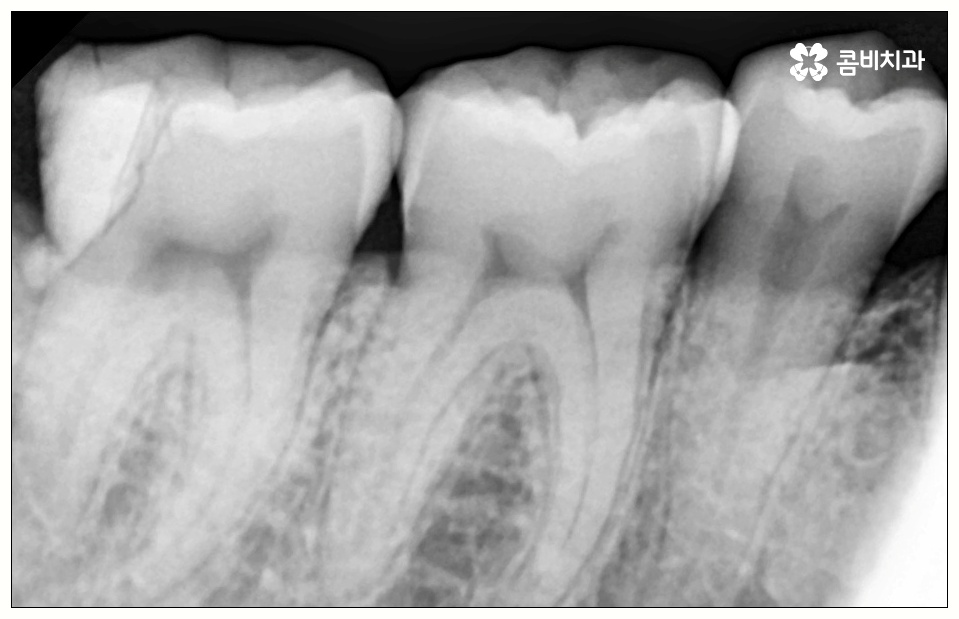

하지만 꼭 발치 처치를 받아야 하는 사랑니도 있는데 그 중 대표적인 것이 바로 어금니 사이 충치 를 유발한 경우로, 비스듬하게 나온 사랑니가 앞의 어금니를 밀면서 압박을 주고 옆면에 충치를 일으키는 등 손상시키고 있다면 늦기 전에 발치 처치를 받으실 필요가 있습니다.

이 때 어금니 뒤쪽으로 비스듬하게 사랑니가 자리를 잡으면 부분적으로 맹출이 되면서 치아 사이에 좁은 틈새가 만들어져 여러 가지 부산물들이 끼기 쉬워지는 반면 칫솔질 등 관리는 더욱 어려워지기 때문에 구강 질환 발생률이 높아질 수 있어요.

위생 관리가 제대로 되지 않으면 치태와 치석이 늘어나 세균이 증식하면서 구취는 물론 충치가 유발되게 되는데, 이것을 방치할 경우 사랑니 자체가 썩어 옆의 어금니로 충치가 옮겨가게 되거나 사랑니와 어금니 사이 충치 발생으로 인해 어금니까지 덧씌워야 하는 상황이 올 수도 있으니 주의하실 필요가 있어요.

특히 어금니 사이 충치 는 눈에 잘 보이지 않을 뿐만 아니라 어느 정도 진행이 될 때까지 통증이 크지 않기 때문에 치료시기를 놓치게 되는 경우가 많이 있는데요.

치아 사이 충치는 법랑질이 두꺼운 교합면, 즉 음식을 잘게 부수는 윗면이 아니라 치아와 치아 사이에 맞닿고 있어 비교적 법랑질의 두께가 얇고 신경까지의 거리가 짧은 옆면에 생기는 것이기 때문에 병증이 진행되는 속도가 빠르고 치료하기가 까다로워 될 수 있는대로 빨리 대처하실 필요가 있어요.

사랑니로 인해 어금니 사이 충치 가 발생하고 치아 파절이 일어나 신경까지 손상이 일어난 경우 원인이 된 사랑니를 발치한 후에 신경 치료와 크라운 처치를 통해 어금니 수복을 해 주게 되는데 이 때 근관 소독 및 밀봉 후 통증이 없어졌다고 해서 크라운 처치를 해 주지 않은 채로 치료를 마치게 되면 2차 감염이 일어나거나 외부 충격으로 인해 또 다시 파절이 생길 가능성이 높아 어렵게 살린 어금니를 잃게 될 수도 있으니 꼭 남아 있는 치아를 전체적으로 덮어주는 크라운 처치를 통해서 보호해 주시는 것을 권유드리고 있습니다.